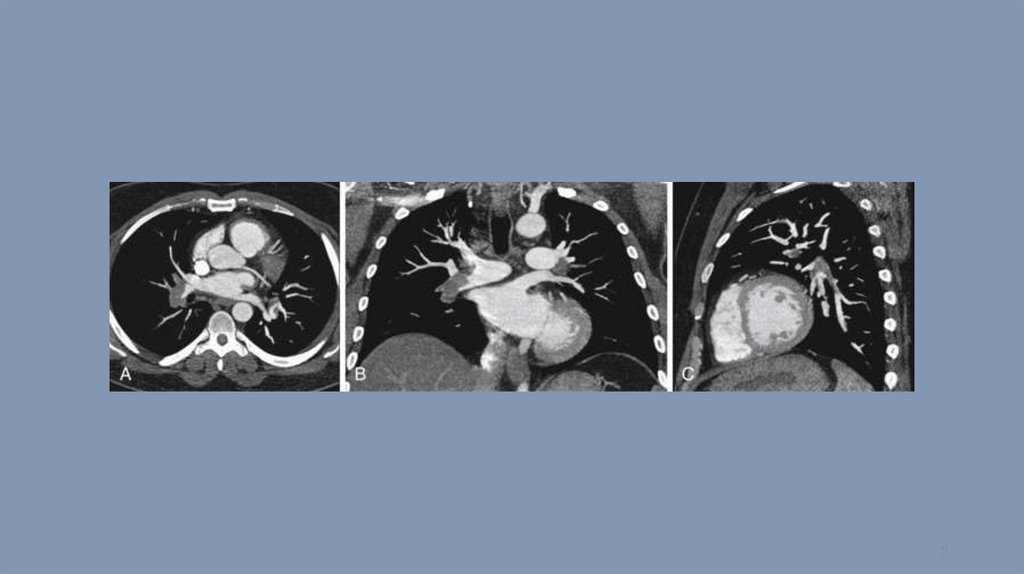

Компьютерная томография. Тест 14